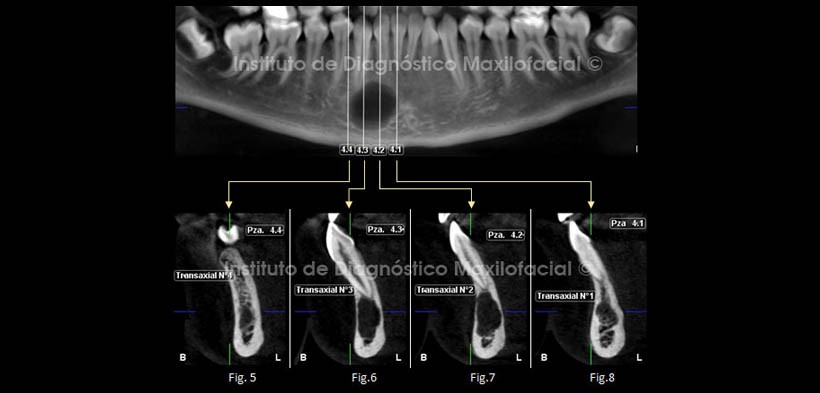

Se realizaron cortes a nivel de las piezas dentarias 4.1, 4.2, 4.3, 4.4 para la evaluación completa de dicha entidad (Fig. 4)

En los cortes transaxiales realizados a diferentes niveles en toda la extensión de la lesión podemos observar a nivel de la pieza 4.1 una imagen hipodensa con disminución del patrón trabecular, a nivel de la pieza 4.2 podemos observar el adelgazamiento de las tablas óseas, así como la erosión de la tabla ósea vestibular, así mismo a nivel de la pieza 4.3 se observa el adelgazamiento de las tablas óseas, no se observa expansión de las corticales. Fig. 5, 6, 7, 8